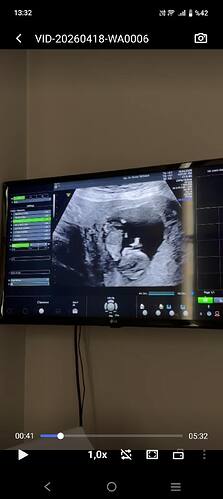

Canım çok net değil ama başka var mı yakin ve net tahmin edecek olursak erkek bebek gibi

Ters duruyor du zaten baş aşağı dı Doktor ne kız dedi ne erkek haftaya konuşuruz dedi kararsız kaldım dedim

Anladım baş aşağı durduğunu orda çıkıntı var o yüzden erkek gibi geldi kordon değil ise